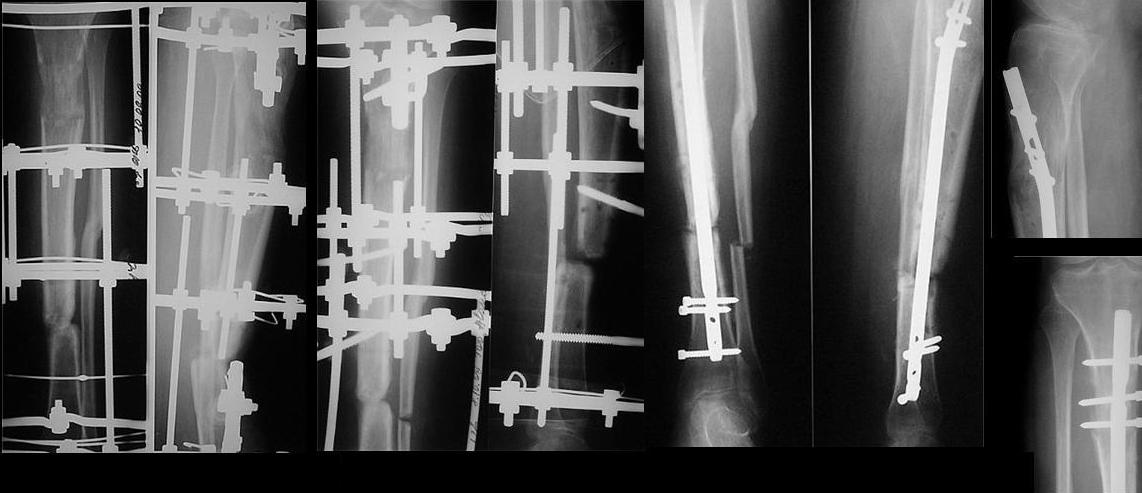

Уважаемые коллеги! Прошу совета.Больная, 32 лет, рабочая, 2,5 года назад в ДТП получила открытый перелом костей левой голени в с/3. В одной из больниц нашего города, где отдают предпочтение накостному остеосинтезу, произведен остеосинтез б/б кости пластиной с 7 отверстиями с иммобилизаций гонитной гипсовой повязкой, почему-то с эквинусной установкой стопы. В послеоперационном периоде наступил некроз кожных покровов, нагноение раны, оголение кости и пластины на протяжении 5 см. Следующие 7 месяцев идет борьба за сохранение пластины, закрытие раны (кожная пластика). Исход - несращение, остеомиелит, функционирующий свищ, миграция винтов. Пластина удалена. И уже в другом лечебном учреждении, произведена резекция концов б/б кости на протяжении 4,5 -5 см., гнойный процесс ликвидирован. Произведено успешное замещение дефекта по Илизарову. Но при стыковке отломков возникла рекурвация голени до 25 град. Все эти годы стопа оставалась в эквинусном положении, конечность не нагружалась. Имеется лимфедема, I cт. Движения в коленном суставе восстановились, а в голеностопном остались на уровне качательных. К нам больная обратилась с просьбой долечить, поскольку прежние доверительные отношения с лечащим врачом по некоторым причинам были нарушены. На голени 4-х кольцевой аппарат: на дистальном и проксимальном кольцах по 3 спицы, на средних - по одной. Аппарат стоит уже 7 мес., нестабилен, мягкие ткани вокруг некоторых спиц воспалены. Продолжить лечение имеющимся аппаратом вряд ли удастся. Наш план дальнейшего лечения: 1. снять аппарат; произвести остеотомию м/б кости, зафиксировать голень спице-стержневым АВФ, попытавшись одномоментно «выставить» ось голени 2. после заживления ран от спиц предыдущего аппарата и полного устранения рекурвации аппаратом, произвести второй этап операции - выполнить БИОС с рассверливанием костномозгового канала.Вопросы: 1. Может быть, следует обойтись только первым этапом, учитывая наличие периода нагноения, и завершить лечение АВФ? 2. Какие неожиданности БИОС технического порядка могут встретиться в данном случае и какие есть «маленькие хитрости» для их преодоления? 3. Проксимальное блокирование вероятнее всего произойдет по регенерату, будет ли оно состоятельным (регенерату около 6 мес.)? 4. Что делать со стопой? Пытаться разработать или планировать удлинение ахиллова сухожилия? Жду совета. Виктор.

Сделан первый этап операции: наложен спице-стержневой аппарат с остеотомией малоберцовой кости на уровне ложного сустава, с захватом переднего отдела стопы полукольцом с целью выведения из порочного положения.

Проксимальное кольцо на стержне Штеймана и Шанца - не будут мешать введению штифта. Дистальное - на двух спицах и стержне. Два промежуточных - по стержню на каждое. Стержни диафизарной части планируем использовать как джойстики, аппаратом дадим компрессию на штифте.

Положение отломков улучшилось. Манипулируя стержнями, в ожидании заживления ран, довправим отломки, попытаемся вывести стопу, насколько успеем. Затем выполним БИОС.

сделан первый этап операции: остеосинтез спице-стержневым аппаратом 7.11.09 г. выполнен второй этап - БИОС с рассверливанием канала, операция прошла без ожидаемых трудностей, открывать зону ложного сустава не пришлось. Прошу сделать замечания.

Виктор Попов, Караганда.

Рекурвация вроде осталась. Недорепонировали на этапе ЧКО.

И точка входа слишком низко.

И гвоздик коротковат imho.

Мы бы сделали заход через переднее межмыщелковое поле, тогда бы динамический блокирующий винт в овальном отверстии прошёл бы через нормальную кость, а не через регенерат. Ну, и стержень, соответственно, потребовался бы длиннее.

Уважаемый коллега! Однозначно надо было произвести первичную динамизацию!!! Мне кажется в целом не плохо сделано, если пациент еще в стационаре не поздно убрать статические винты. Иначе остеотомированный м/б кость ч/з 3 нед срастется и будеть распоркой. С уважением Ерсин Жунусов.

"Рекурвация вроде осталась. Недорепонировали на этапе ЧКО. точка входа слишком низко динамическое блокировани, гвоздик коротковат imho

Небольшие технические погрешности вряд ли кардинально повлияют на окончательный результат. Я бы поздравил уважаемого Виктора с успешным решением трудной задачи с использованием новой технологии и, самое главное, больную с реальным появлением надежды на выздоровление после длительного периода применения предшествующей конструкции с сомнительным прогнозом на исход.